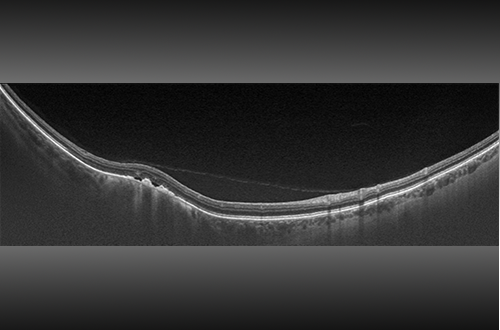

- L’ultra-grand champ avec OCT intégré Swept-Source facilite un examen détaillé de la rétine, du vitré à la sclère.

- L’OCT Swept-Source guidé ultra-grand champ permet de visualiser les pathologies en tout point de l’optomap.

- Source lumineuse OCT 1050 nm, pour une pénétration plus profonde des tissus et une imagerie claire et détaillée de la choroïde

| Imagerie OCT | Type de signal : Diffusion optique du tissu Signal Source: OCT Swept-Source, longueur d’ondes 1050 nm Puissance optique : Laser de classe 1 répondant à la norme IEC/EN60825-1:2014(2007) Résolution axiale type : <7 micron Résolution transversale : <20 micron Scanners: Galavanometric with x, y pair Profondeur du balayage : Jusqu’à 2,5 mm |